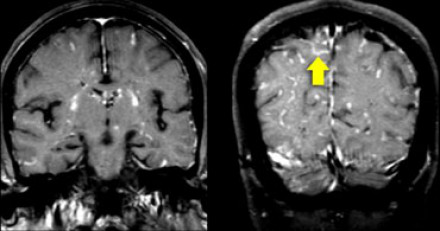

多發(fā)性增強病灶的鑒別診斷

圖片二

在上圖中,是各種多發(fā)性增強白質(zhì)病灶圖像,我們對其中部分病例進行詳細討論。需要說明的是,以下鑒別診斷中提到的疾病與上圖中的圖像并不完全重合。

血管炎

大多數(shù)血管炎性疾病的MRI成像特點是點狀增強。

腦部血管炎常見于系統(tǒng)性紅斑狼瘡、結(jié)節(jié)性多動脈炎(PAN)、白塞病(Behcet)、梅毒、韋格納肉芽腫(Wegener)、干燥綜合征(Sjogren)和原發(fā)性中樞神經(jīng)系統(tǒng)血管炎。

白塞病(Behcet)

白塞病更常見于土耳其患者。典型MRI表現(xiàn)是急性期出現(xiàn)腦干病灶結(jié)節(jié)性增強。

其他疾病的腦轉(zhuǎn)移病灶

其他疾病的腦轉(zhuǎn)移病灶周圍常包裹有水腫帶。

交界區(qū)腦梗死

周圍交界區(qū)腦梗死在病變早期可出現(xiàn)增強病灶。